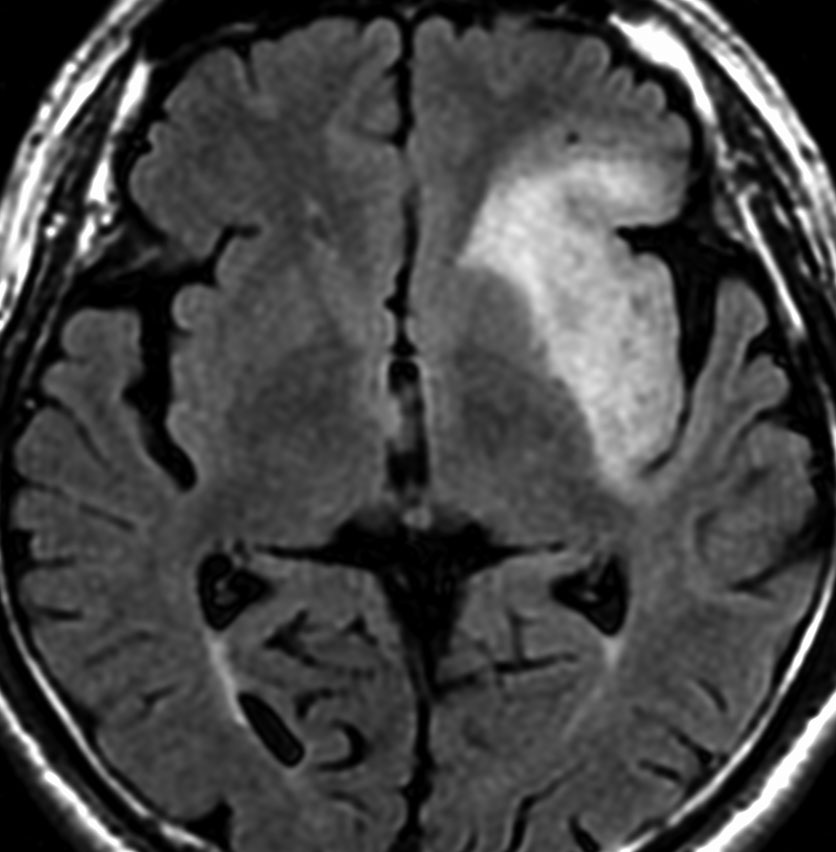

2010年無症状の時の画像です。こんなのを手術で摘出したら認知機能が落ちて人格が変わります。だから経過観察しました。

2015年のテモゾロマイドを開始する前の画像です。2014年にちょびっと生検術をして1p/19q欠失,IDH変異はわかっていました。2015年に全般発作を起こしたので治療を開始しました。テモゾロマイドを 2年 24コース続けました。乏突起膠腫は大きくなる時,てんかんを生じることが多いです。

2020年の画像です。腫瘍はかなり小さくなって再燃(再発)していません。てんかんも抑制されて発作はありません。無症状です。

この例は,手術も放射線治療もしないで,乏突起膠腫が10年以上,制御できることを示しています。また,テモゾロマイド治療でてんかん発作が少なくなることも有名な事実です。

でも,現実はこんなに甘くない?  2025年時点で,治癒を目指すなら低線量放射線治療を加えるべきと考えられています。